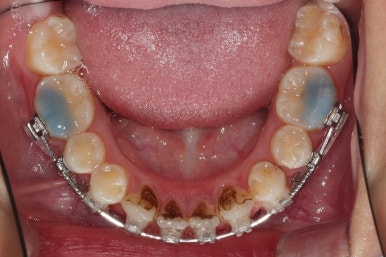

초진 시 입안의 모습입니다.

위아랫니가 많이 삐뚤진 않는데 뭔가 이상하죠?

어금니 맞물림은 지그재그로 잘 맞물려 있는데 위아래 앞니는 서로 앞뒤로 매우 멀죠.

비밀은 매우 자연스러워 보이지만 아래 앞니 2개가 선천 결손인 상태였습니다.

앞니끼리 맞물리지 않다보니 아래 앞니는 점점 솟구쳐 과개교합(깊게 맞물려 아래 앞니가 거의 보이지 않는 현상)이 되게 됩니다.